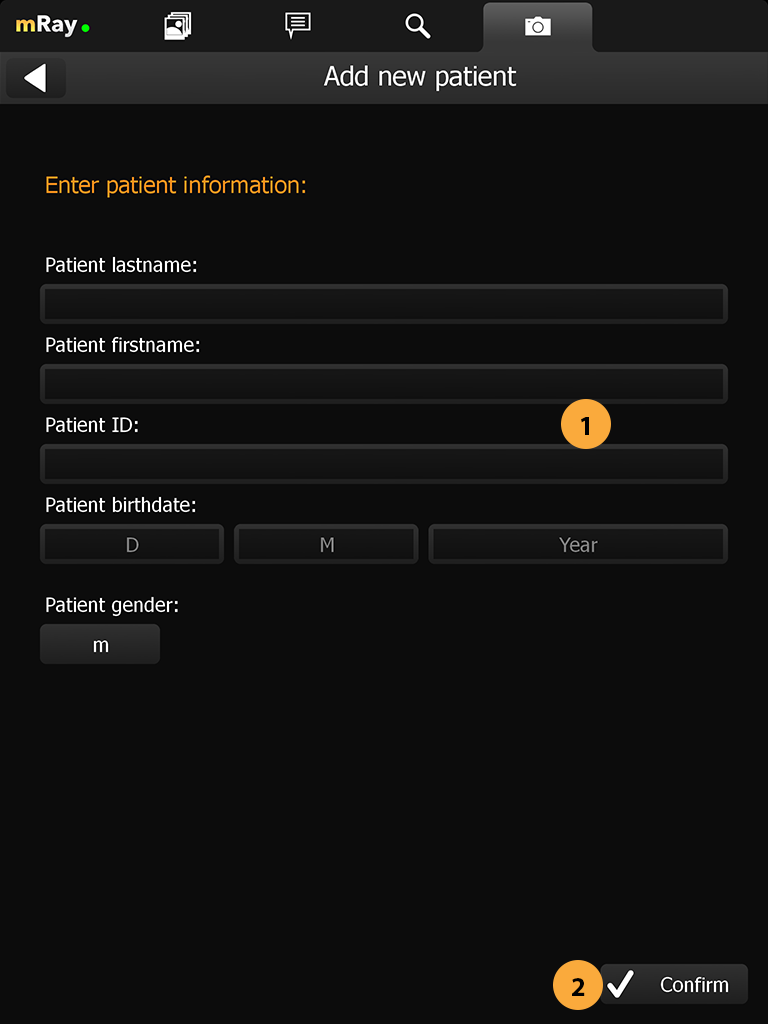

15.5. Patient form

If you have decided to manually add the desired patient, the following view will open. The required tags for the patient are displayed at Point 1 and setup by your pacs administrator. Make sure to enter the correct information before proceeding to the next step.

-

Input fields for the patient information defined by your PACS.

-

Confirm the input and continue with the next step.